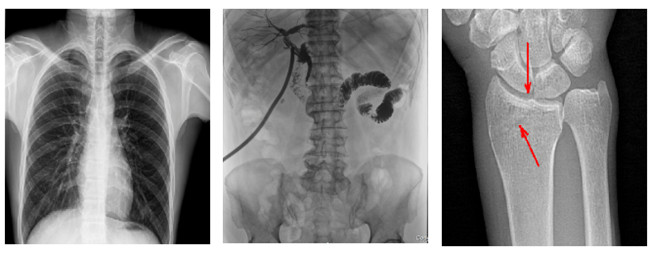

普利德多功能懸吊動態(tài)DR,搭載100μm高品質動態(tài)平板探測器,不僅滿足常規(guī)的數(shù)字化X線全身攝影需求,同時還擁有數(shù)字攝影、數(shù)字透視、數(shù)字造影、全景拼接等多種功能,極大地拓展了X線檢查在臨床應用范圍,為醫(yī)院臨床應用帶來更多實用價值。基于百微平板的高清成像,圖像清晰度與分辨率更高,可滿足不同檢查部位對細節(jié)成像的高品質要求,在胸腹部、脊柱等復雜骨骼和軟組織的攝片上應用,更便于觀察隱匿性病灶,精準識別疑難病癥。

不同于靜態(tài)DR拍攝隱匿性病灶時,由于組織重疊病灶難辨,耗費時間更長且易漏診、誤診,普利德多功能懸吊動態(tài)DR可通過動態(tài)實時連續(xù)成像,對于重疊部位病灶或者易被遮擋的病灶進行多角度動態(tài)觀察,毫秒級時間內實現(xiàn)動靜態(tài)轉換點片,快速、精準完成攝片。比如隱匿性肋骨骨折,可在透視下觀察患者的呼、吸過程,避開重疊影像,快速點片,保證檢查部位的病癥不被遺漏,實現(xiàn)精準診斷。